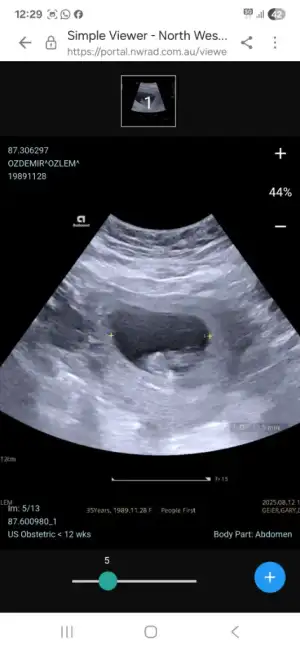

Screenshot_20250812_122843_Samsung Internet.webp

ba

Eklentiler

• Screenshot_20250812_192152_Instagram.webp

Screenshot_20250812_192152_Instagram.webp

11,3 KB · Görüntüleme: 13

• Screenshot_20250812_122954_Samsung Internet.webp

Screenshot_20250812_122954_Samsung Internet.webp

18,6 KB · Görüntüleme: 11

• Screenshot_20250812_122943_Samsung Internet.webp

Screenshot_20250812_122943_Samsung Internet.webp

20,9 KB · Görüntüleme: 8